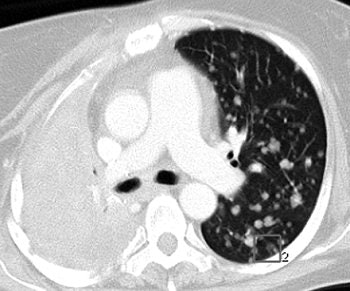

| A 47-year-old woman with numerous metastatic nodules from small cell lung cancer in right lung and unmatched nodule in superior segment of left lower lobe. Above, transverse CT image shows baseline findings. Below, transverse reformatted CT image shows follow-up findings. Overall matching rate was 0 (0/10). Infiltration of lung cancer was markedly increased, with complete collapse of upper lobe of right lung during interval. |